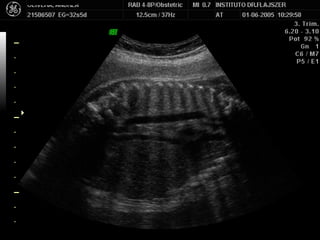

1) LONGITUDINAL / CEFALICA / DORSO IZQ

Apex y estómago: ¿Cerca o lejos del transductor? Lejos Long/Cef/D.izq

2) LONGITUDINAL / PODALICA / DORSO DER

Apex y estómago: ¿Cerca o lejos del transductor? Long/Pod/D.der Lejos